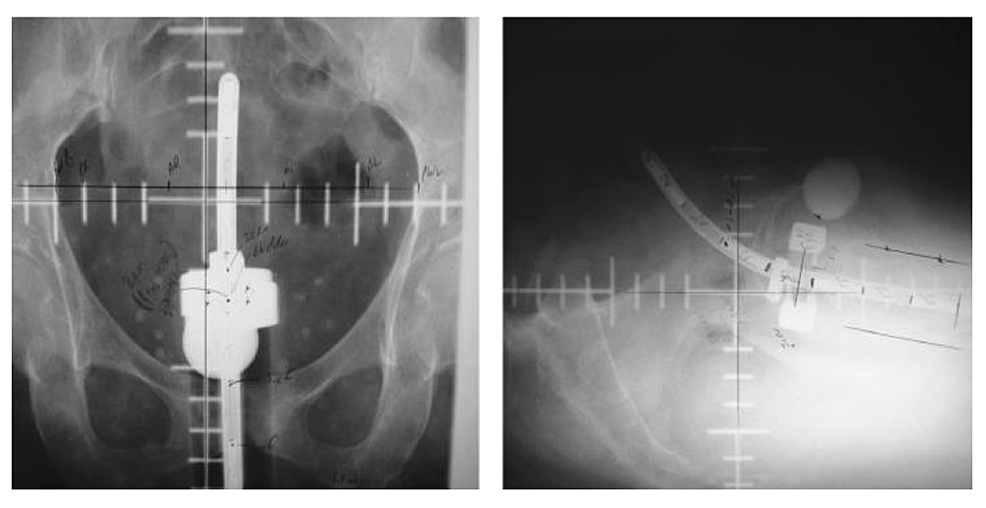

Frontiers Combined Interstitial and Intracavitary HighDose Rate Brachytherapy of Cervical Cancer

Figure 1 from The use of transapplicator intracavitary ultrasonography in brachytherapy for Intracavitary Brachytherapy Applicators learn about the applications, techniques, and outcomes of intracavitary brachytherapy for cervical, uterine, and. intracavitary brachytherapy uses an applicator to introduce radioactive sources into natural (eg, vagina) or surgical (eg, lumpectomy). easy to use ct/mr brachytherapy applicators adaptable for a diverse patient population. Tandem and ovoids, used in definitive treatment of cervical cancer. Elekta's wide array of. Intracavitary Brachytherapy Applicators.